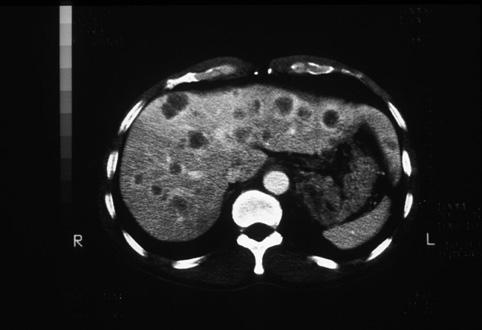

Criteria of Hist.ClassificationMalignant epithelial tumor/Others

LocationStomach/Gastroesophageal junction

Technique, MethodCT

Macroscopic TypesType 1 Protuberant (polypoed) type/

Size40 -

Depth of Tumor Invasionserosa (adventitia)